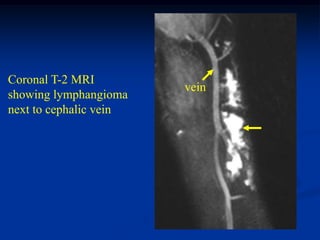

Case #1213

46 year male with

lymphangioma arm

Axial PD MRI

Another T-2 MRI

showing 2 lesions

Coronal T-2 MRI

vein

showing lymphangioma

next to cephalic vein

Sagittal T-2 MRI   vessels

showing hygroma

next to brachial

vessels